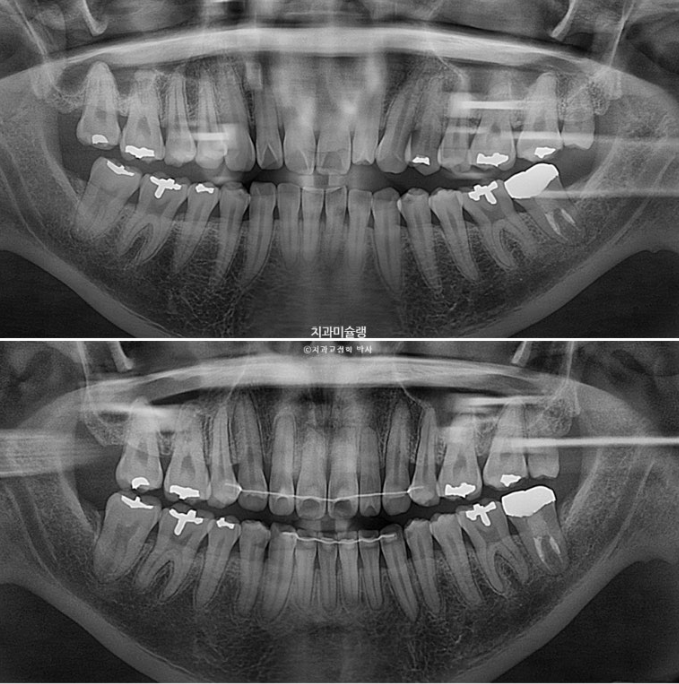

If we compare the before-and-after X-rays,

2022.12~2025.12

The upper front teeth were intruded by 2 mm. Thanks to that, gum exposure when smiling decreased, and the gummy smile was resolved.

The front teeth moved back a great deal, but the key point is that they did not become over-inclined inward.

During the three-year treatment period, root resorption occurred in the upper front teeth.

Because the amount of backward movement of the front teeth was so large, and because we focused on moving the roots backward more than the crowns to prevent excessive inward tipping, this was unavoidable.

The root parallelism is good.